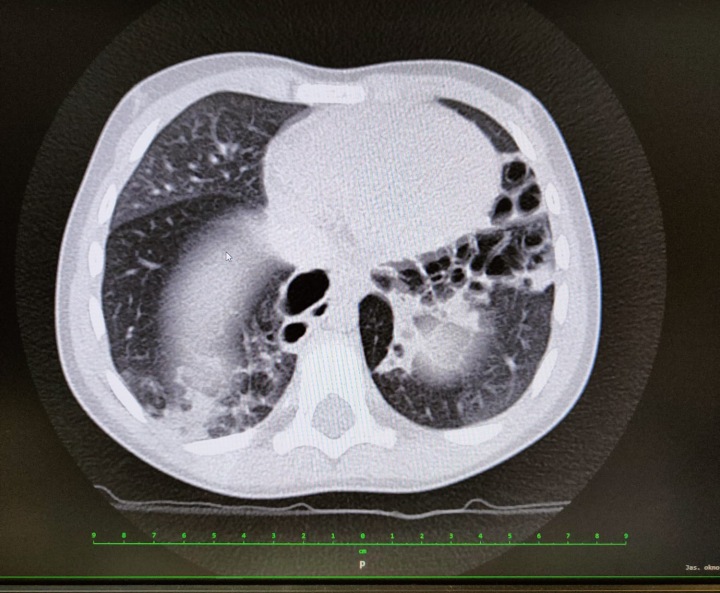

Rentgen Aniččiných plic.

Rentgen Aniččiných plic. Zdroj: archiv rodiny Aničky, se svolením